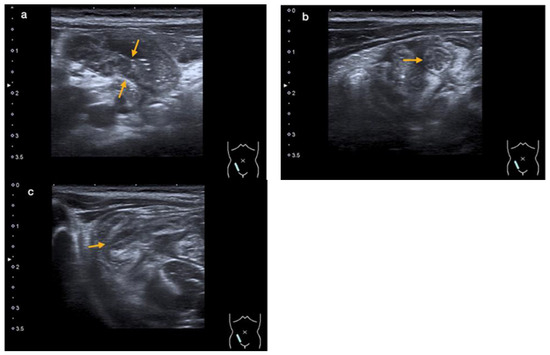

2.3. Diagnostic Evaluation

3.3. Diagnostic Evaluation